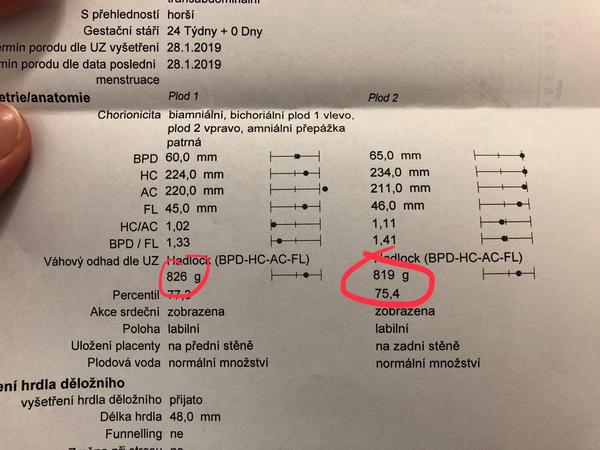

@vilmic hezká váha. A taky si vem že máš dvě placenty,vepředu a vzadu,ty taky něco váží,pak voda..dělají si pěkné domečky,bobci.

Já budu mít asi nějaký váhový odhad až ve 30 tt i když k Dr chodím co 14 dní. Před 14 dny měl odhad 410 g,teď počítám tak 600? Oni už prcci rychle rostou a přibírají.

@seveneye čoveče ne, jednička je holka. Asi bude pořádná po mamince.. 😂😂 Ale my jsme s mužem oba velký. Já mám v normálním stavu 175 cm a kolem 70 kil a muž má tak 188 a 110 kilo má určitě. Asi nemají po kom být malý. Syn měl 3460 g a 52 cm a to se narodil 37+4..

Tak to fakt nemají být po kom,i starší byl solidní. U dvojčat je super když se narodí s váhou jako běžná miminka. O starost míň 🙂